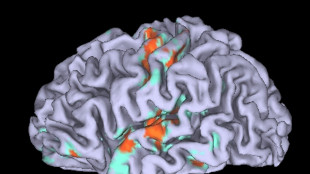

Conservatori o progressisti, lievi le differenze nel cervello

Lo dimostra uno studio su quasi mille persone